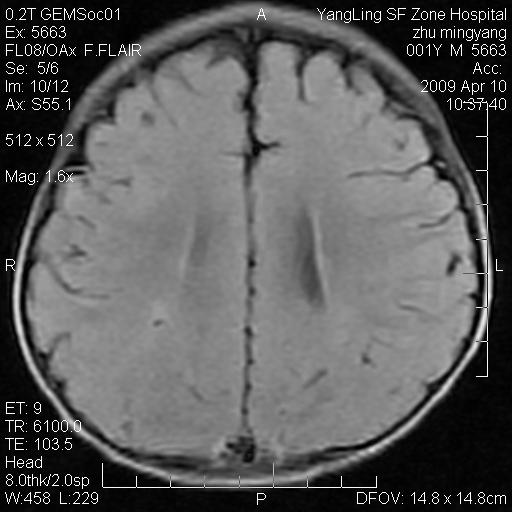

患者:1岁半,两天前外伤收住我院,ct检查小脑占位

考虑星形细胞瘤,建议增强

髓母细胞瘤或血管母细胞瘤,增强后可以鉴别;影像资料见 <。鱼博浪老师的《中枢神经系统ct与mr鉴别诊断》 小脑部肿瘤章节。

髓母细胞瘤或血管母细胞瘤!支持!

支持考虑髓母细胞瘤

考虑----髓母细胞瘤可能性大

考虑髓母细胞瘤或室管膜瘤。

支持髓母细胞瘤。

考虑髓母细胞瘤。

考虑髓母细胞瘤或星形细胞瘤

考虑髓母细胞瘤.

考虑髓母细胞瘤可能性大。

小脑肿瘤.考虑髓母细胞瘤可能.

就病灶部位及临床资料首先考虑髓母.